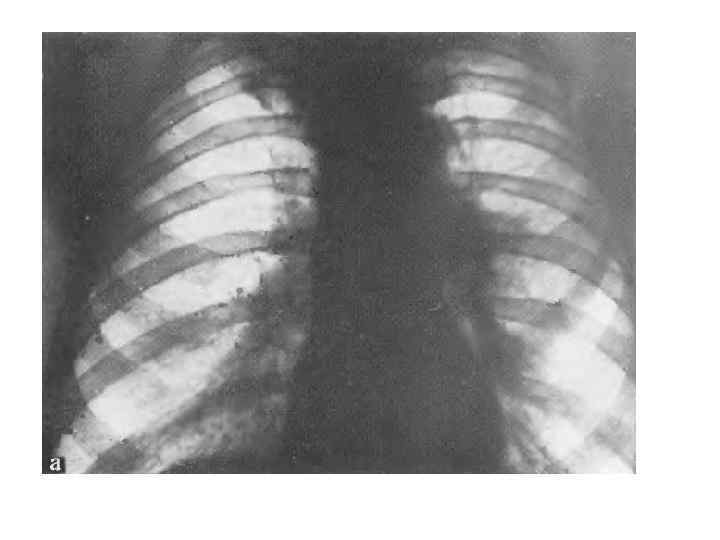

Рис. 235. Ателектаз нерхней доли. а — прямая рентгенограмма; 6 — боковпя'ренттенограмма. Смещение дачи вверх и кпереди.